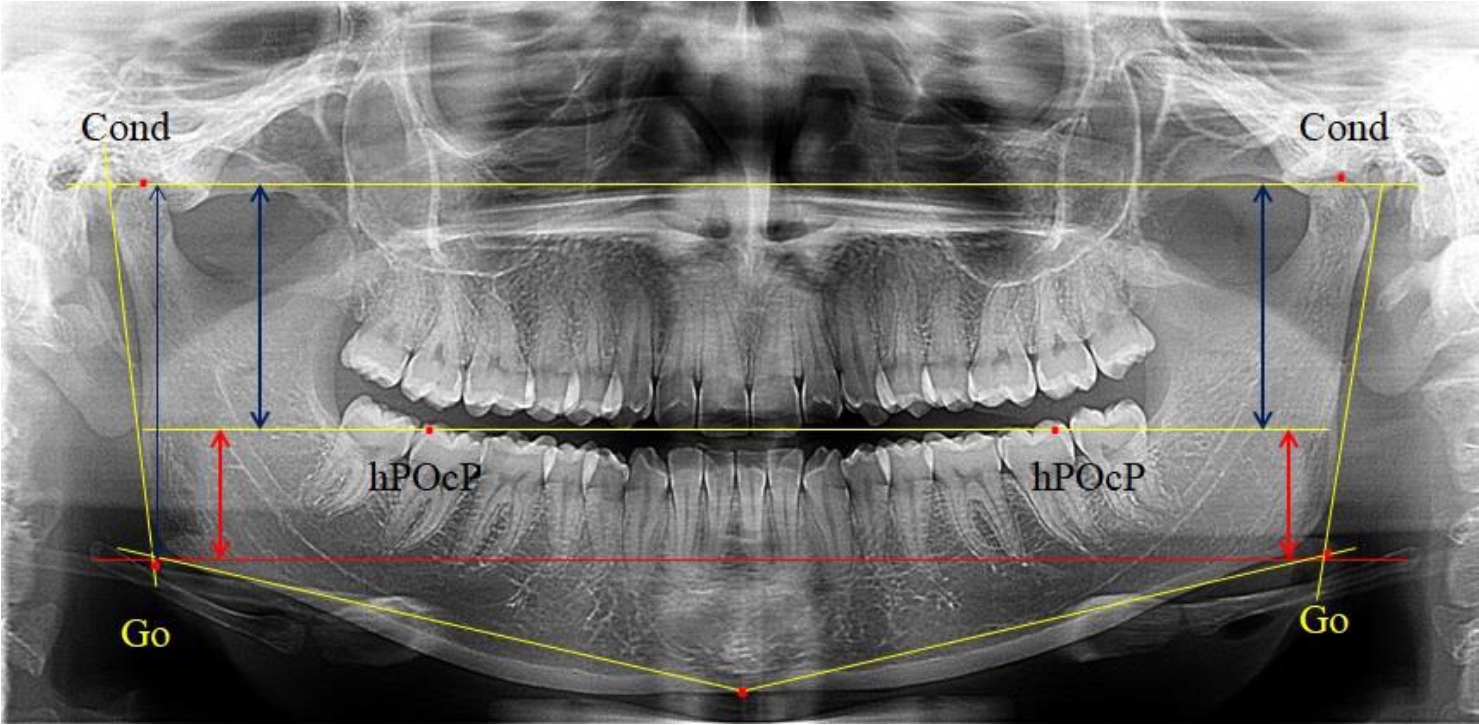

На боковых телерентгенограммах определяли положение верхней точки суставной головки Cond. Касательные линии к ветви и телу нижней челюсти пересекались в точке, которую в клинической практике обозначают как точка угла нижней челюсти или точка гонион Go. Точкой hPOcP обозначали дистальный бугорок нижнего второго моляра вблизи окклюзионного контура коронки, через нее от межрезцовой точки проводили окклюзионную линию, ее продолжали до задней части ветви челюсти. Высоту ветви измеряли как расстояние от угла нижней челюсти до вершины суставной головки Go-Cond. Общую высоту ветви условно делили на 2 части, ее границей служила окклюзионная линия. Верхнюю часть обозначали как окклюзионно-суставная, а нижнюю – как окклюзионно-гониональная.

На ортопантомограмме использовали аналогичные суставные точки Cond на каждой стороне, их соединяли между собой суставной линией Cond-Cond.

Касательная к ветви нижней челюсти соединяла выступающие точку. При построении касательной к телу челюсти проводили в обе стороны линии от точки Gn, расположенной в нижней центральной части подбородочного симфиза, до выступающей нижней точки угла челюсти. Касательные линии при пересечении определяли конструктивную точку гонион Go. Соединение гониональных точек определяло положение гониональной линии Go-Go. При соединении окклюзионных точек hPOcP получали окклюзионную горизонталь (рис. 1). Измеряли расстояние между горизонталями в области ветвей нижней челюсти. Статистический анализ проводили в программе Microsoft Excel. Составляли вариационные ряды с последующим расчетом среднего значения, стандартного отклонения и ошибки среднего ±m. Также оценивали максимальные и минимальные значения величин. Определи относительные величины соотношения верхней и нижней частей ветви нижней челюсти.

Рис. 1. Метод измерения высоты ветви нижней челюсти на телерентгенограмме (а) и ортопантомограмме (б)